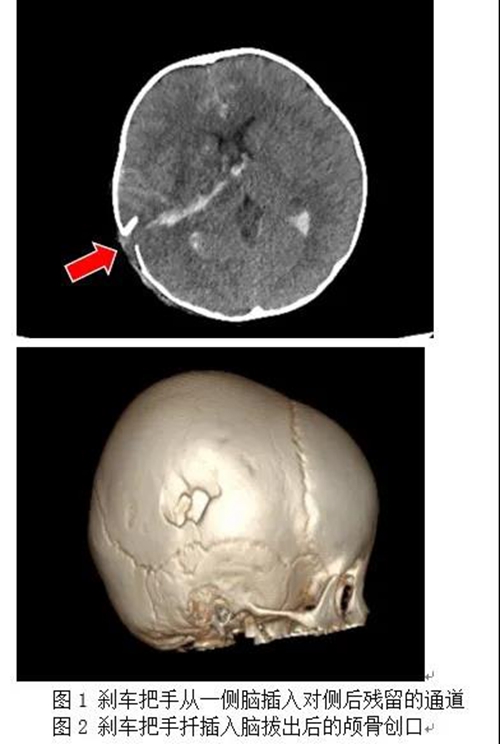

當時,2歲的糖糖在外面玩耍時不慎碰倒了路旁的電動車,電動車剎車把手插入孩子的顱內。驚慌失措的糖糖家人趕緊將電動車從孩子身上搬走,并撥打“120”急救電話求救。

滿頭是血的糖糖被“120”緊急轉入青島婦女兒童醫(yī)院兒童急診意外傷害門診。因穿通傷導致大腦嚴重受傷,糖糖一直處于抽搐昏迷狀態(tài),兒童創(chuàng)傷科醫(yī)生馬上為患兒進行病情評估和鎮(zhèn)靜止驚治療,在控制患兒驚厥持續(xù)狀態(tài)后醫(yī)護人員立刻通過“兒童嚴重創(chuàng)傷綠色通道”將其轉入兒童重癥監(jiān)護室(PICU)。

經麻醉科、檢驗科、輸血科多方積極準備,糖糖到院后1個小時就順利進入手術室,手術開始!術中,兒童創(chuàng)傷科(神經外科)孫勇主任主刀,第一時間為糖糖清除嵌入腦組織內粉碎的顱骨殘片、快速控制因腦部血管撕裂導致的出血并清除壞死腦組織。由于患兒是異物腦穿透傷,術后腦組織極有可能出現繼發(fā)嚴重腦水腫,孫勇主任憑借多年的危重顱腦損傷搶救經驗,決定去除右側大面積骨瓣以幫助糖糖度過術后的顱高壓危險期,同時放置腦室內顱內壓監(jiān)測裝置,以便術后進行重癥神經監(jiān)護管理,為患兒爭取更好的預后。